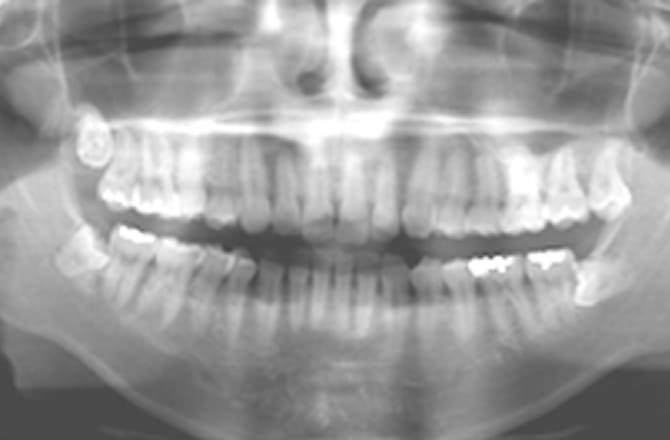

従来のレントゲンとの違い ~立体で把握~

従来のレントゲンでは2次元の平面画像しか得られません。

一方、歯科用CTを用いると3次元の立体画像が得られるので、平面画像ではわからなかった歯やあごの骨の詳細な立体構造や神経の位置などを精度高く把握することができ、より適切な診断・治療が可能になります。

-

従来のパノラマレントゲン

2次元の平面画像のみ

歯科用CT

立体で把握